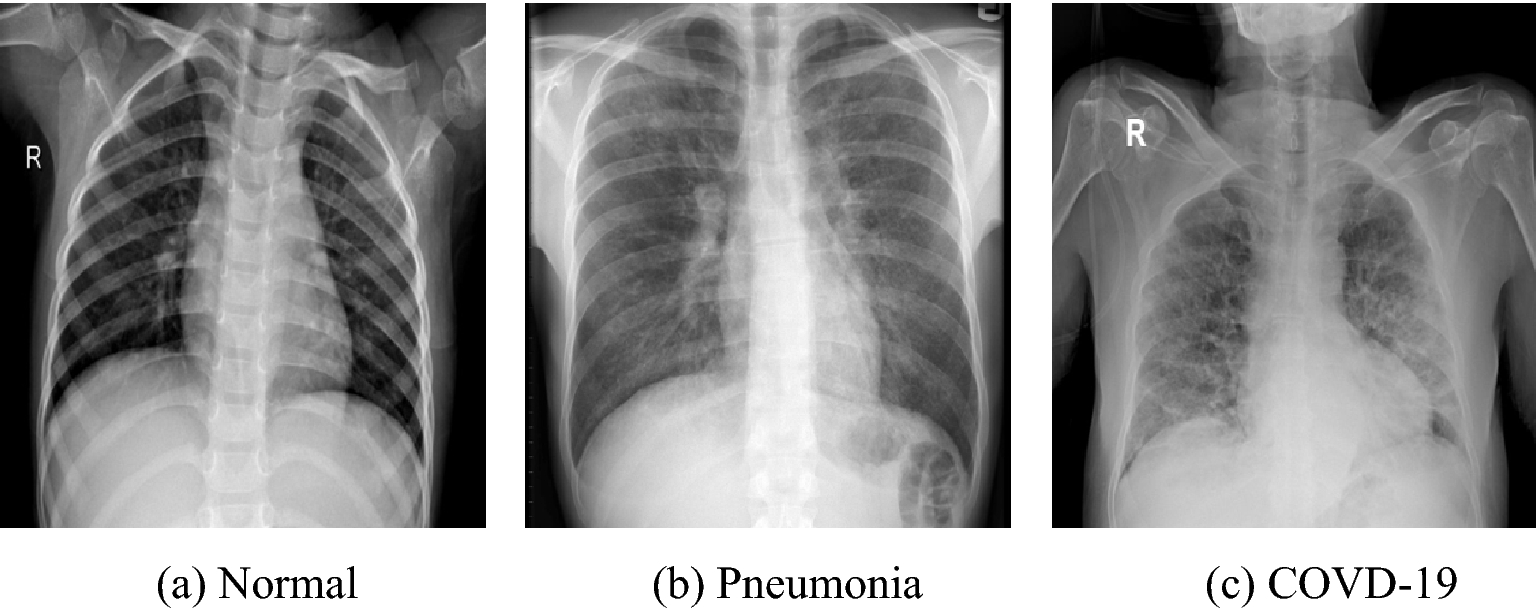

CLEAR: A Clinically-Grounded Tabular Framework for Radiology Report Evaluation

Yuyang Jiang, Chacha Chen, Shengyuan Wang, and 8 more authors